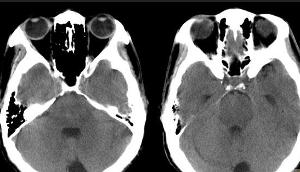

5.CT,MRI檢查,腦CT約半數顯示異常,炎性滲出物充填基底池及腦外側裂,部分患者腦實質內顯示結核瘤,直徑0.5~5cm,單發或多發,多位於額,顳及頂葉,增強掃描顯示環狀強化或密度增高。

6.腦CT檢查 北京兒童醫院自1986~1992年對50例結腦患兒做腦CT檢查發現最常見異常為腦積水(66%),其次為腦梗死(34%),腦萎縮(16%),腦水腫(12%),結核瘤(10%),鈣化灶(8%)及硬膜下積液(4%),只10%患兒無異常所見。